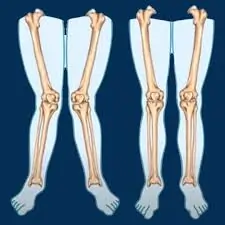

મોબિલિટી એક્સરસાઇઝ (Mobility exercises) આધુનિક ફિટનેસ અને રિહેબિલિટેશન (પુનર્વસન) દિનચર્યાઓનો એક આવશ્યક ભાગ બની ગઈ છે. ભલે તમે રમતવીર હોવ, ફિટનેસના શોખીન હોવ અથવા બેઠાડુ જીવનશૈલીને કારણે જડતાનો સામનો કરી રહ્યાં હોવ, તમારી ગતિશીલતા (mobility) સુધારવાથી તમારા જીવનની એકંદર ગુણવત્તામાં નોંધપાત્ર વધારો થઈ શકે છે. સાચા અર્થમાં ફક્ત સ્ટ્રેચિંગ કરવા કરતાં અલગ, મોબિલિટી એક્સરસાઇઝ સાંધાની…